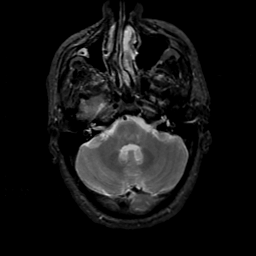

MR Study #18, July 21, 1991 -- Slice #11